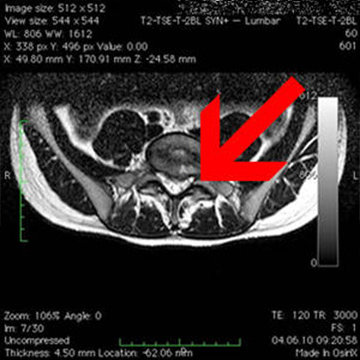

Comment diagnostique-t-on une hernie discale?

En plus du diagnostic clinique, une hernie discale est diagnostiquée ou confirmée à l'aide de l'imagerie à résonance magnétique (IRM).

Bandscheibenvorfall L5 S1 praeoperativ transversal Bandscheibenvorfall L5 S1 praeoperativ transversal